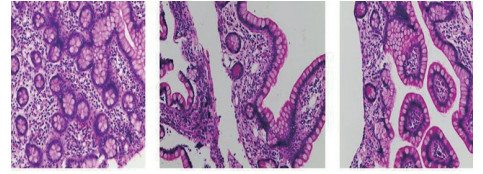

| 图 2 电子结肠镜病理(2017-12-19):示大量嗜伊红细胞,胞质丰富,核深染,细胞表面可见粉红色嗜酸颗粒 |

| 图 3 腹腔镜探查+坏死空肠切除+大网膜切除+肠系膜上动脉探查+空回肠双腔造口术后病理(2018-1-19):可见部分肠壁全层坏死,合并慢性炎症,肉芽组织增生 |

1 资料与方法患者男,30岁,因“腹胀、腹痛6 d,高热1 d”于2017年12月11日由广州南沙区中心医院转诊收入中山大学孙逸仙纪念医院全科医学科。患者本次起病前无明确病因或明显诱因。患者以左上腹轻微胀痛起病,进行性加重。南沙区医院查血常规:白细胞14.27×109/L,血小板50×109/L,中性粒细胞比例74.5%,嗜酸粒细胞1.02×109/L,嗜酸粒细胞比例7.2%。全腹CT+CTA提示:门静脉左右主干及其小分支栓子形成。后在3 d内连续复查血常规,提示血小板进行性下降,由50×109/L相继降至35×109/L、18×109/L;(嗜酸粒细胞计数及比例未能提供),并出现高热(体温39.5℃),因病情危重,遂转诊本院。入院时患者精神疲乏、高热,腹部胀痛难忍,伴有咳嗽。查体:体温38.6℃,心率87次/min,血压102/76 mmHg,指尖血氧饱和度90%~91%。双肺呼吸音粗,双肺均可闻及小水泡音。腹部稍膨隆,叩诊鼓音,左上腹及脐周轻压痛,无反跳痛。听诊肠鸣音减弱,约1~2次/min。当天查血常规示白细胞11.85×109/L,血小板23×109/L,中性粒细胞比例58.1%,嗜酸粒细胞3.5×109/L,嗜酸粒细胞比例29.5%。凝血常规提示:PT 15.9S,PTA 51.1%,PT/R 1.39,Fbg 1.59 g/L,PTINR 1.39,APTT 35.2 s,D-二聚体114.36 mg/L FEU(参考值范围0~0.55 mg/L FEU)。胸部+全腹部CT+CTA示“门静脉主干及左、右支、肠系膜上静脉近端栓子形成;腹主动脉及左侧髂总动脉小附壁血栓;左肺上叶尖后段、左肺上叶下舌段、右肺中叶及双肺下叶炎症;乙状结肠两段节段性管壁增厚,建议排外占位性病变;腹水、盆腔积液,大网膜炎性病变可能性大”。每日复查血常规,发现血小板进行性下降,最低至15×109/L(参考值范围125~350×109/L),嗜酸粒细胞计数及比例进行性升高,分别达到8.07×109/L(参考值范围0.020~0.52×109/L)和51.1%(参考值范围0.4-8.0%)。每日复查凝血常规亦提示凝血指标不断恶化,纤维蛋白原最低降至0.63 g/L。在予禁食、“美平(美罗培南)”抗感染、输注纤维蛋白原及血小板、维护水电解质平衡及营养支持的积极治疗的同时,还积极完善了以下检查寻找病因:①血液系统方面:血浆鱼精蛋白副凝实验:阳性(+);凝血功能实验:PT 15.5S↑,PTA 47.8%↓,PT/R 1.35↑,PTINR 1.36↑,APTT 40.4 s↑,AT-Ⅲ 57.7%↓,F-VII 32.8%↓,F-Ⅷ 68.1%↓,F-X 68.0%↓,F-XII 24.0%↓;纤维蛋白降解产物:381.4 mg/L↑;血栓弹力-血小板图:R时间10.3 min↑;角度18.5度↓;最大血块强度13.2 mm↓;MA(ADP)值5.6 mm↓。骨髓病理学:嗜酸性粒细胞增多(43%),巨核细胞减少(7个)。慢淋/淋巴瘤表型分析:获取和分析细胞数5.0万;粒细胞区百分比82.6%;淋巴细胞区百分比9.4%;单核细胞区百分比2.0%;CD45dim细胞区百分比1.3%;有核红及细胞碎片区域百分比4.6%。ETV6/PDGFRB融合基因、FIP1L1/PDGFRA融合基因(—)。骨髓细胞学病理结果:符合嗜酸细胞增多症;②消化系统检查:大便细菌培养鉴定及药敏提示无志贺、沙门菌生长,有真菌生长;大便难辨梭菌毒素检测(—);粪便找寄生虫、找阿米巴、寄生虫七项均为(—);消化肿瘤系列提示CA-125 244.8 U/mL↑;腹腔穿刺术穿出“血性腹水”,腹水CA-125 1006.0 U/mL↑,腹水找癌细胞(—);复查腹部CT+CTA:乙状结肠两段节段性管壁增厚,建议进一步检查;排外占位性病变;遂行PET-CT:提示全身未见明确恶性征象。行电子结肠镜示:内镜诊断:(1)回肠末段炎症;(2)乙状结肠炎症;(3)内痔。钳取组织送病理,提示:标本①(回肠末端)黏膜组织呈慢性炎,伴糜烂,一些嗜酸性粒细胞浸润(约35个/HPF);②(乙状结肠)黏膜组织呈慢性炎,伴糜烂,个别嗜酸性粒细胞浸润(约4个/HPF)。③风湿免疫系统方面:免疫八项、风湿四项:C反应蛋134.0 mg/L,余未见异常;总IgE 170 IU/mL↑;抗ENA抗体、狼疮两项、血管炎两项、免疫球蛋白G4、抗心磷脂抗体三项均为阴性;④其他感染病原学检查:乙肝、肝炎系列、性病三项、痰找抗酸杆菌、T-spot实验、流行性出血热、登革热抗体、登革热病毒NS1抗原、外斐氏试验、肥达氏试验、痰结核培养、骨髓培养、血液细菌、血液厌氧菌培养均为阴性。经过上述检查,初步考虑“特发性嗜酸性细胞增多症”,于12.15开始予“甲泼尼松龙40 mg静滴, 1次/d”及“低分子肝素0.6 ml皮下注射, 1次/d”抗炎抗凝治疗。患者病情及检验指标有所好转,热退、腹胀减轻,血常规提示血小板升至49 ×109/L,嗜酸粒细胞计数和比例均下降至正常,凝血常规提示D-二聚体降至47.90 mg/L FEU。但12-22患者自行进食多量米饭后突发腹胀痛较前加重,急查血常规提示白细胞升至21×109/L,血小板再次下降至15×109/L,D-二聚体升至97.28 mg/L FEU,全腹CTA提示“门静脉主干及左、右支、肠系膜上静脉近端新发栓子形成”,遂于当日转至ICU予“尿激酶20万U+肝素钠1250 U”溶栓治疗后予“低分子肝素0.6 ml皮下注射, 1次/12 h”序贯抗凝治疗。后患者病情渐渐稳定,至2018-1-18患者在“甲泼尼松龙12 mg口服, 1次/d”及“立伐沙班20 mg口服, 1次/d”的维持治疗下,血小板、嗜酸粒细胞计数及纤维蛋白原均回复正常,D-二聚体下降至3.52 mg/L FEU。但遗憾的是,此时患者再次进食大量米饭,约1 h后突发腹痛、气促,急行胸片+腹平片提示:“双侧膈下游离气体,考虑胃肠道穿孔可能;双下肺少许炎症,少量胸腔积液;腹部多量积气伴肠腔扩张”。遂即送手术室行全麻下“腹腔镜探查+坏死空肠切除+大网膜切除+肠系膜上动脉探查+空回肠双腔造口术”,术后病理提示标本①(大网膜)脂肪组织,部分坏死,合并慢性炎,伴一些中性粒细胞浸润,较多泡沫样组织增生,未见明确血栓,未见恶性改变。②(部分空肠)肠壁组织,部分肠壁全层坏死,合并慢性炎,肉芽组织增生,未见明确血栓,未见恶性改变。免疫组织化学:CD38浆细胞(+)、IgG(+)、IgG4(﹣)。术后继续予“立伐沙班10 mg/d”和“甲泼尼松龙8 mg/d”口服治疗,并于2018.2.4停用“甲泼尼松龙”。2.28复查全腹CTA,仍可见“脾静脉新发血栓,门静脉及肠系膜上静脉血栓较前好转”。3.20行空回肠双腔造瘘管泛影葡胺造影术提示“双腔造瘘管通畅,右中下腹小肠蠕动尚可,结肠各段及直肠通畅,未见对比剂外漏征象”。但患者合并了严重的短肠综合征,致严重低钾低钠血症和继发的代谢性脑病,病情再度转危。继续纠正电解质紊乱、补充营养,最终病情好转后于4.11行“造瘘口回纳修补术”。随访半年,患者仍口服“立伐沙班10 mg/d”抗凝治疗,复查血常规、凝血常规等各项指标均正常,但营养状况较差。